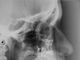

Prognatismo

Casos clínicos - Prognatismo

Paciente 11